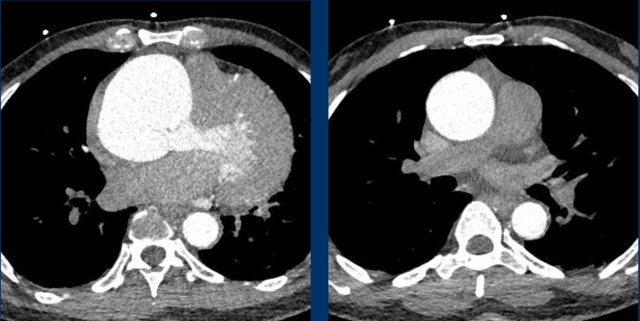

Scroll through the images of a patient with atrial fibrillation.

What are the findings?

Images

The left atrium is dilated.

There is a thrombus in the left atrial appendage (arrow) extending towards the left atrium (arrowhead).

In the left atrial appendage there is often the imaging differential of a thrombus or incomplete opacification due to slow-flow, especially in early contrast phase imaging.

This might be solved with CT in a later contrast phase or acquisition in the prone position.

Transesophageal cardiac ultrasound is considered the gold standard.